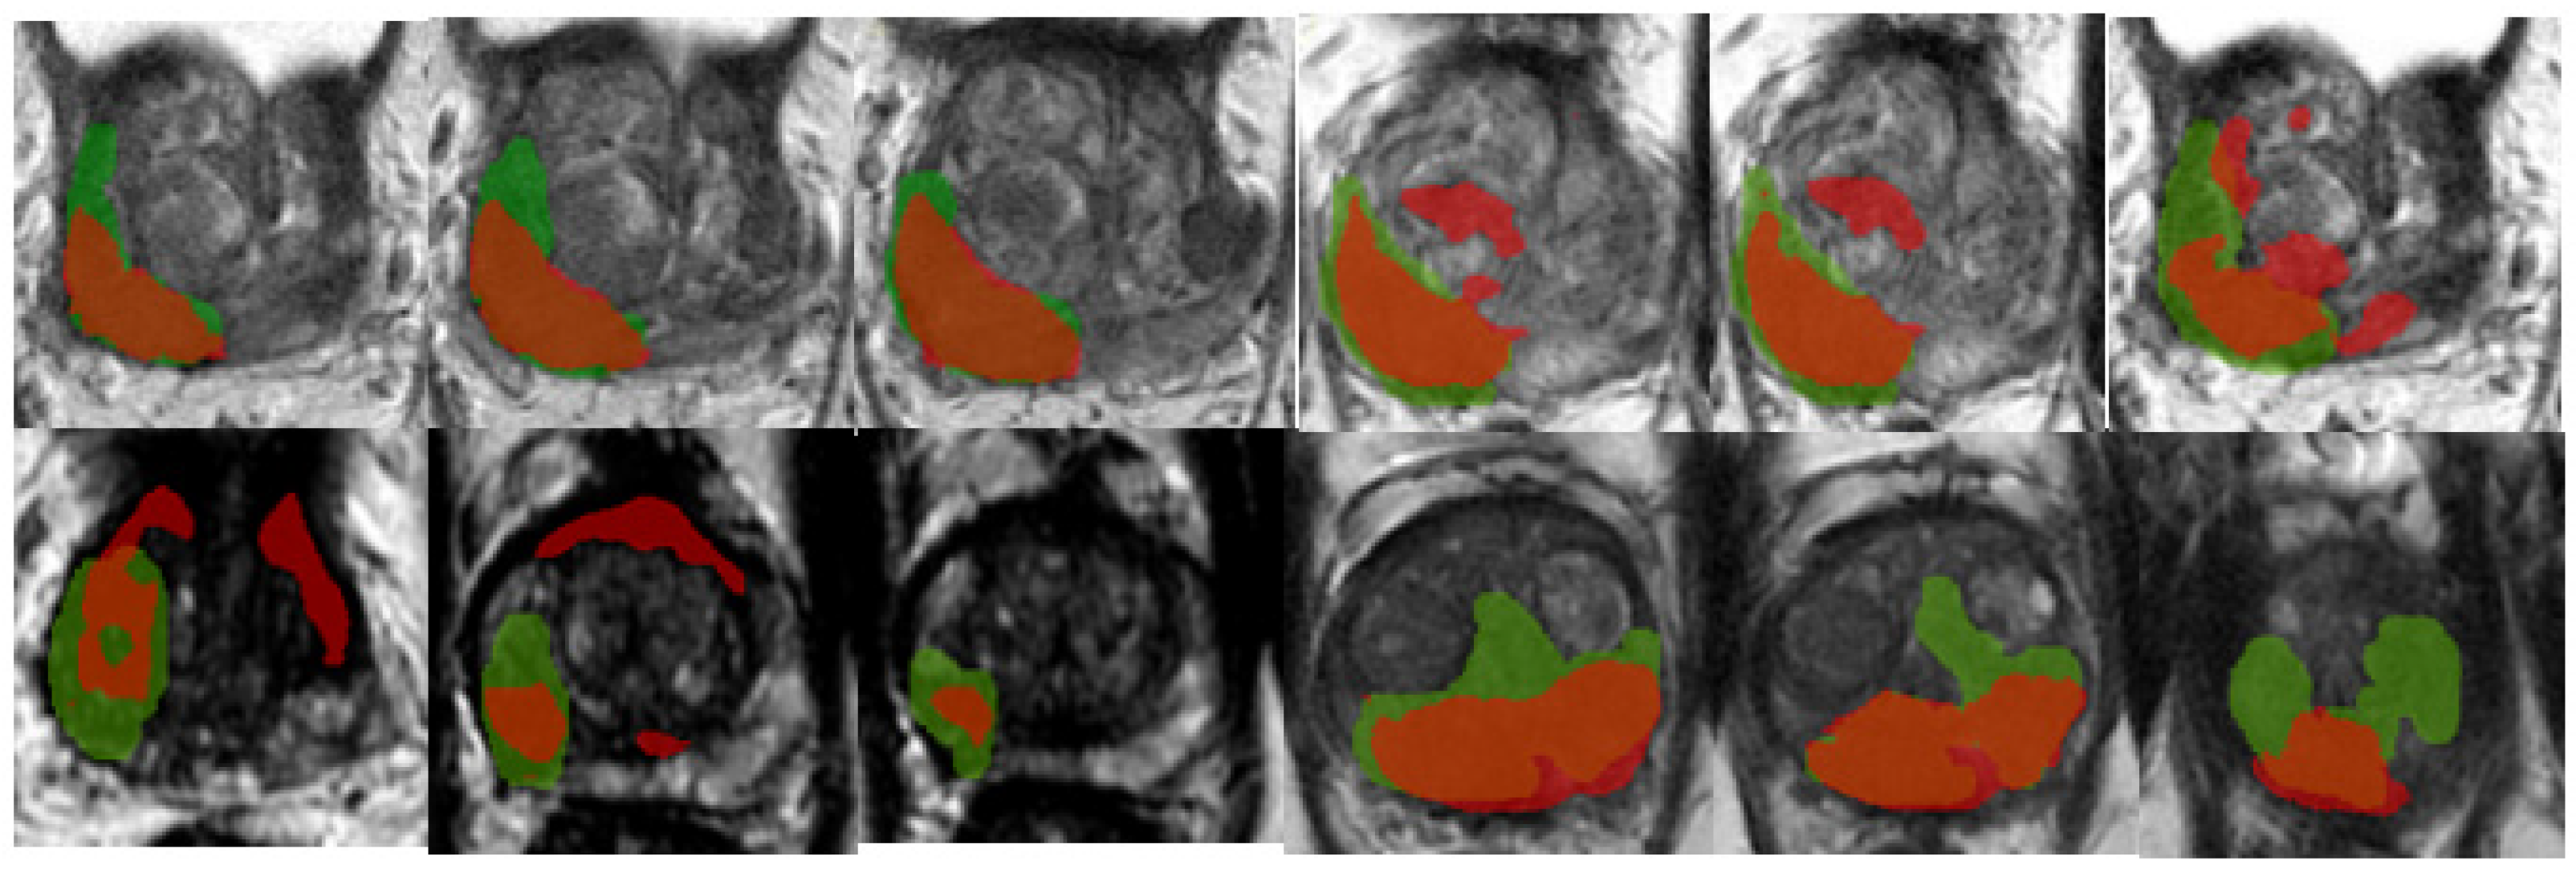

An example of segmentation of cancer foci by the final 2D cancer segmentation model is shown in Figure 17.

Figure 17. Segmentation of cancer by the final 2D segmentation model.

Algorithms 19 00085 g017